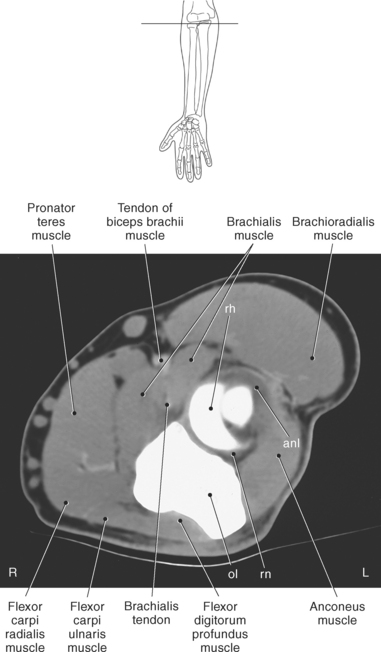

The elbow is a complex hinge-pivot joint created by the articulations of the humerus, radius, and ulna. All three articulations communicate with each other within a single joint capsule. The radius and ulna are the bones of the forearm, with the radius located on the lateral side. The radioulnar and radiohumeral articulations create the pivot joint that aids in supination and pronation of the elbow. The radiohumeral and ulnohumeral articulations form the hinge joint that allows for flexion and extension (Figures 9.70 through 9.73).

The distal portion of the humerus has two distinct prominences termed the medial and lateral condyles, with associated epicondyles, that provide attachment sites for tendons and ligaments (Figure 9.70). The medial epicondyle serves as the site of origin for the common flexor tendon, pronator teres muscle, and medial collateral ligament, whereas the lateral epicondyle serves as the attachment site for the common extensor tendon, supinator muscle, and lateral collateral ligament. Just lateral to the medial epicondyle along its posterior surface is a shallow groove containing the ulnar nerve. Two depressions located on the distal humerus are the anterior coronoid fossa and the deep posterior olecranon fossa. These depressions accommodate the coronoid and olecranon processes of the proximal ulna (Figures 9.70, 9.71, and 9.73). The distal humerus has two cartilage-covered articular surfaces—the capitellum and the trochlea for articulation with the radius and ulna (Figure 9.71). The lateral of the two surfaces is the capitellum, a rounded projection that articulates with the concave surface of the radial head. The trochlea is more medial and has the appearance of an hourglass if viewed in the horizontal plane. The shape of the trochlea helps keep the ulna in position during flexion between the distal humerus and proximal radius (Figure 9.73).

The radius is a long, slender bone with a proximal portion that consists of the radial head, neck, and tuberosity. The radial head has a flat cartilage-covered depression or fossa (fovea of the radius) that articulates with the capitellum of the humerus. In addition, the articular circumference of the radial head articulates against the radial notch of the ulna during supination and pronation. The radial head is attached to the body of the radius by the narrow radial neck. Located at the distal portion of the neck on the medial side of the radius is a roughened projection termed the radial tuberosity. The radial tuberosity serves as the attachment point for the biceps brachii muscle (Figures 9.72 through 9.74).

The ulna is located medial within the forearm. The proximal ulna consists of the olecranon and coronoid processes and the trochlear and radial notches. The superficial dorsal surface is formed by the hook-shaped olecranon process, which is the attachment site for the triceps brachii. The trochlear notch is a half-moon-shaped concave articular surface that curves around the trochlea of the humerus. This articulation allows for flexion and extension of the elbow. Located on the anterior portion of the distal end of the trochlear notch is a small beaklike process called the coronoid process. Just distal and lateral to the coronoid process is a flattened depression called the radial notch. It is covered by articular cartilage for articulation with the radial head. Immediately distal to the coronoid process is a roughened bony surface termed the ulnar tuberosity. The tendon of the brachialis muscle inserts on both the coronoid process and the ulnar tuberosity (Figures 9.72, 9.73, 9.75, and 9.76).